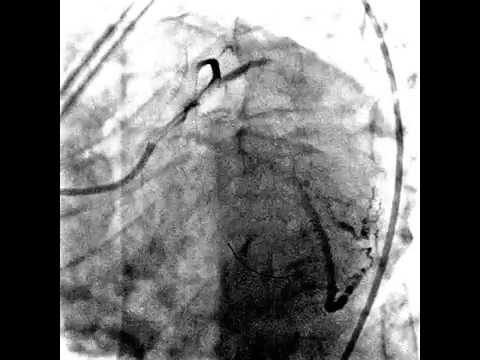

Этот метод — «золотой стандарт» в диагностике ишемической болезни сердца (ИБС). Это рентгеноконтрастное исследование, которое с большой точностью позволяет определить характер, место и степень сужения коронарной артерии. И тем самым решить вопрос о выборе и объёме проведения таких медицинских процедур, как коронарное шунтирование и баллонная ангиопластика. Коронарография проводится при помощи рентгеноконтрастного препарата в специализированных рентгенооперационных, которые оснащены высокоточным оборудованием.

Методика является малоинвазивной, поэтому во время процедуры пациент находится в сознании. После проведения местной анестезии специалисты приступают к исследованию — вводят специальный катетер через бедренную артерию и верхнюю часть аорты в просвет коронарных артерий. В ряде случаев катетер проводится через артерию предплечья, что уменьшает время наблюдения за больным после выполненной коронарографии.

Затем через катетер вводят рентгеноконтрастное вещество, которое кровотоком разносится по коронарным сосудам. Данный процесс фиксируется при помощи специальной установки — ангиографа. Результат выводится как на монитор, так и помещается в цифровой архив.

Коронарография – это современный инвазивный способ проверки сосудов, несущих кислород к сердечной мышце. Данный способ является рентгенологическим. Благодаря нему после введения в сосуды контрастного вещества можно выявить различные патологии сердца и сосудов, питающих орган.

Проведение коронарографии – это способ, широко использующийся в терапии, кардиологии и кардиохирургии современного времени. Благодаря данному методу врачам удается не только вовремя обнаружить дефекты в работе органа, но и своевременно устранить их, проведя операцию в режиме реального времени. При введении контрастного вещества в сосуды, врачи могут полностью оценить кровоток пациента и точно локализовать закупорку или уменьшение просвета коронарной артерии.